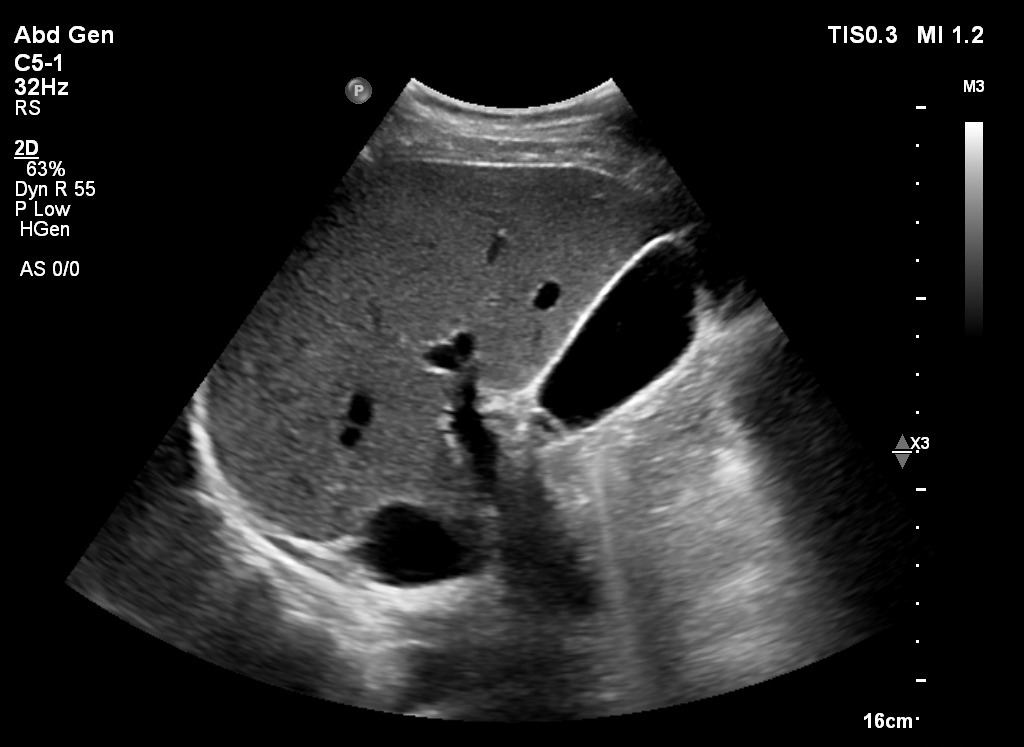

Pamje ne eko te melcise gjate ekzaminimit me ultratinguj

Gjatë ekografisë abdominale, mjeku përdor një sondë që rrëshqet mbi bark dhe, përmes valëve zanore, krijon pamje të organeve të brendshme.

Ekzaminimi ndihmon për të vëzhguar dhe vlerësuar gjendjen e:

• Mëlçisë;

• Fshikëzës së tëmthit;

• Pankreasit;

• Veshkave;

• Shpretkës;

• Fshikëzës së urinës;

• Enëve të mëdha të barkut.